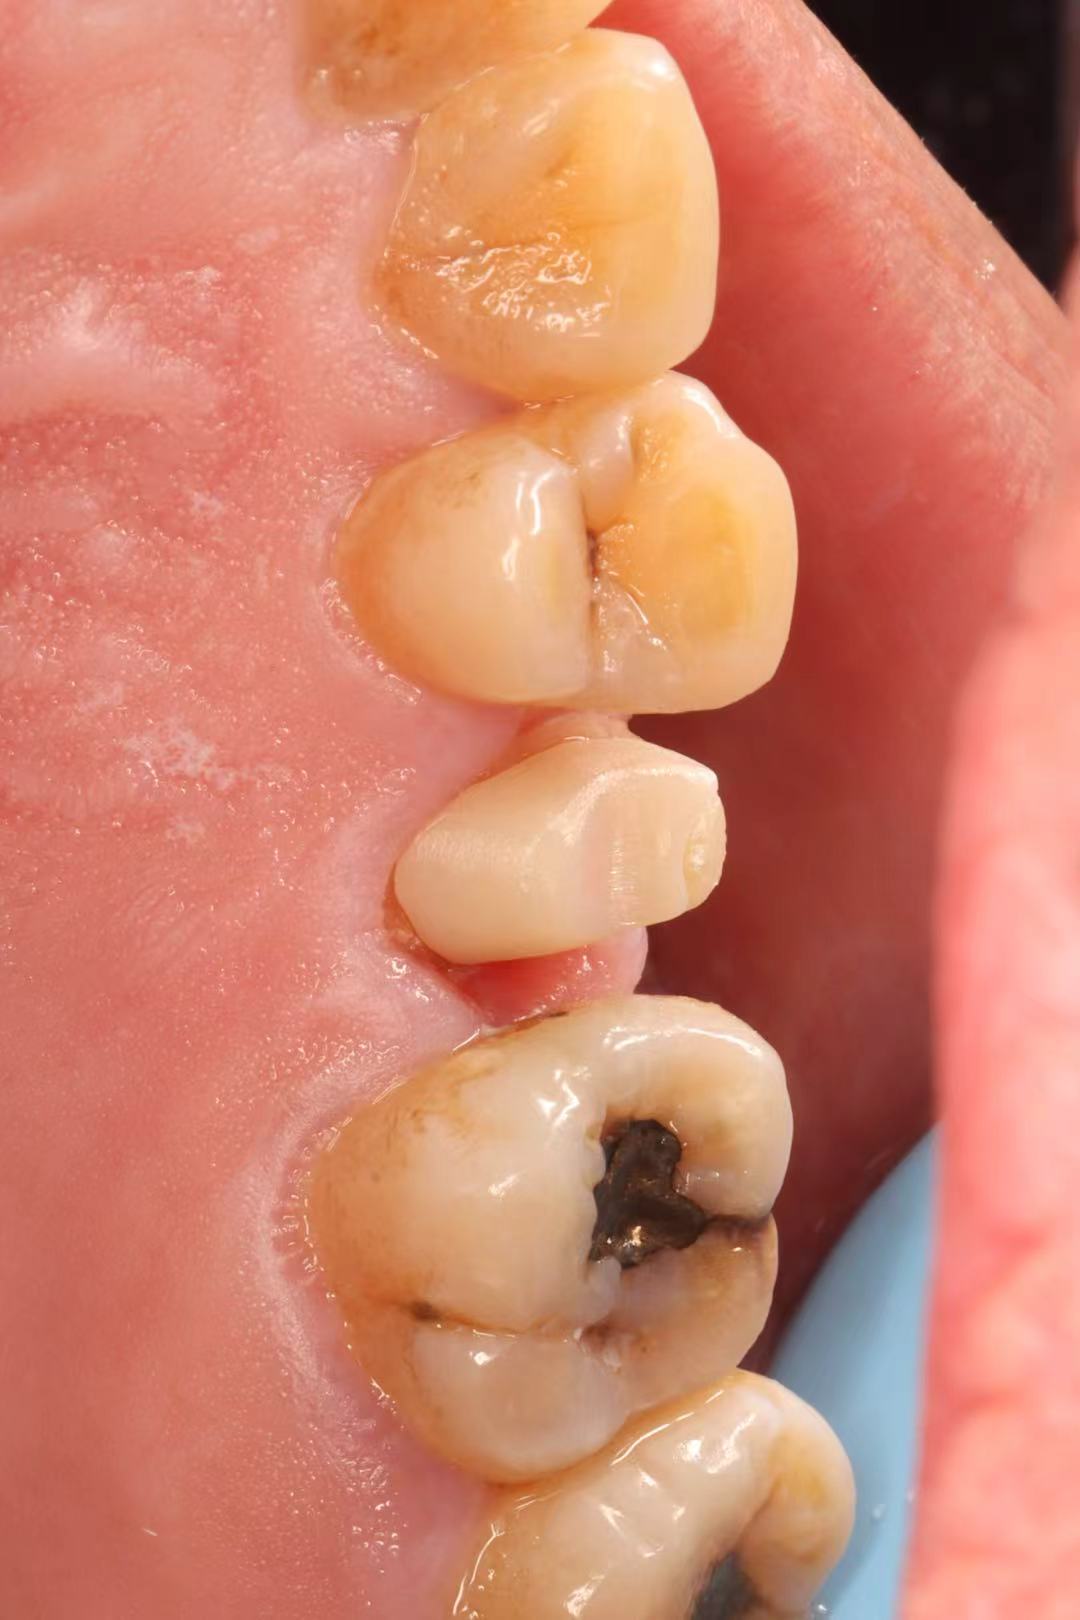

June 20, 2025: The patient's chief complaint is that endodontic treatment was performed on the right maxillary posterior tooth abroad, and a deep carious lesion has been recently detected, requiring restoration. The following are the intraoral photographs taken upon the patient's first visit: a large carious lesion is visible on the occlusal surface of tooth 15 (FDI numbering), with only the buccal wall remaining. Percussion test and cold-hot stimulation test showed no response, and yellow obturation material is visible at the root canal orifices.

Treatment Plan: Given the patient’s refusal of extraction and implant placement, conservative treatment is adopted: retreatment of the root canal followed by post-and-core restoration.